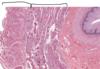

Esophagus – mucosa, submucosa, muscularis externa

Esophagus – mucosa – stratified squamous non-keratinized ep, lamina propria with small blood vessels, muscularis mucosa (smooth muscle)

Esophagus - submucosa (DICT) with blood vessels